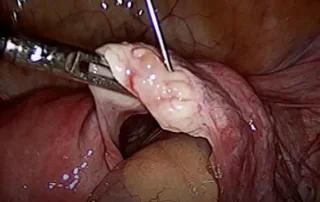

Uterine Artery Ligation at the Isthmus: A Simplified Technique for effective Haemostasis in Laparoscopic Myomectomy

DOI: 10.36205/trocar7.2026005